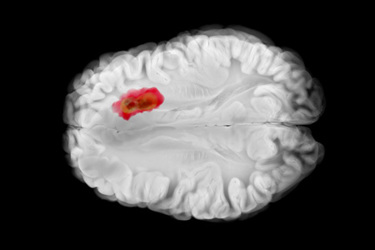

About 15 years ago, Mike Ciesielski, Ph.D., and colleagues at Roswell Park Cancer Institute in Buffalo spun off their research targeting survivin, a cell-survival protein found in most glioblastomas and many other cancers. Today, they are running a randomized Phase 2b trial studying their peptide mimic immunotherapeutic vaccine, SurVaxM, for glioblastoma.

Mike Ciesielski, Ph.D.: SurVaxM is a cancer vaccine that targets a protein called survivin, which is expressed by tumor cells to help them live longer. Tumor cells take advantage of that protein, allowing them to resist chemotherapy by plugging up the autodestruct program and allowing themselves to live longer. It's an oncofetal protein, meaning that it's normally expressed during fetal development but then turned off shortly thereafter and not expressed in adult tissue. It makes a nice target to immunize patients against.